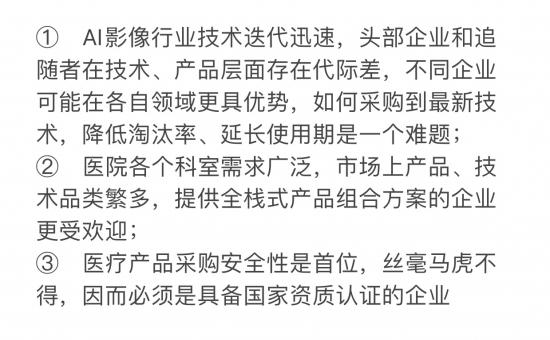

AI技术目前处于发展初期,技术迭代迅速,对医院来说也是一件既“甜蜜”又“忧伤”的事情。

对大型综合性医院来说,采购AI影像技术和产品是一件慎之又慎的事情,“甜蜜”指相比之前现在“有得选”,“忧伤”指的是企业太多“不好选”。

医院采购的三个难题

综合以上三个难题,最受医院欢迎也即商业化更具优势的AI影像企业模型应当是:具备国家资质认证,全面或至少主要领域技术领先或持平其他企业,提供全栈式产品解决方案,省心省力。